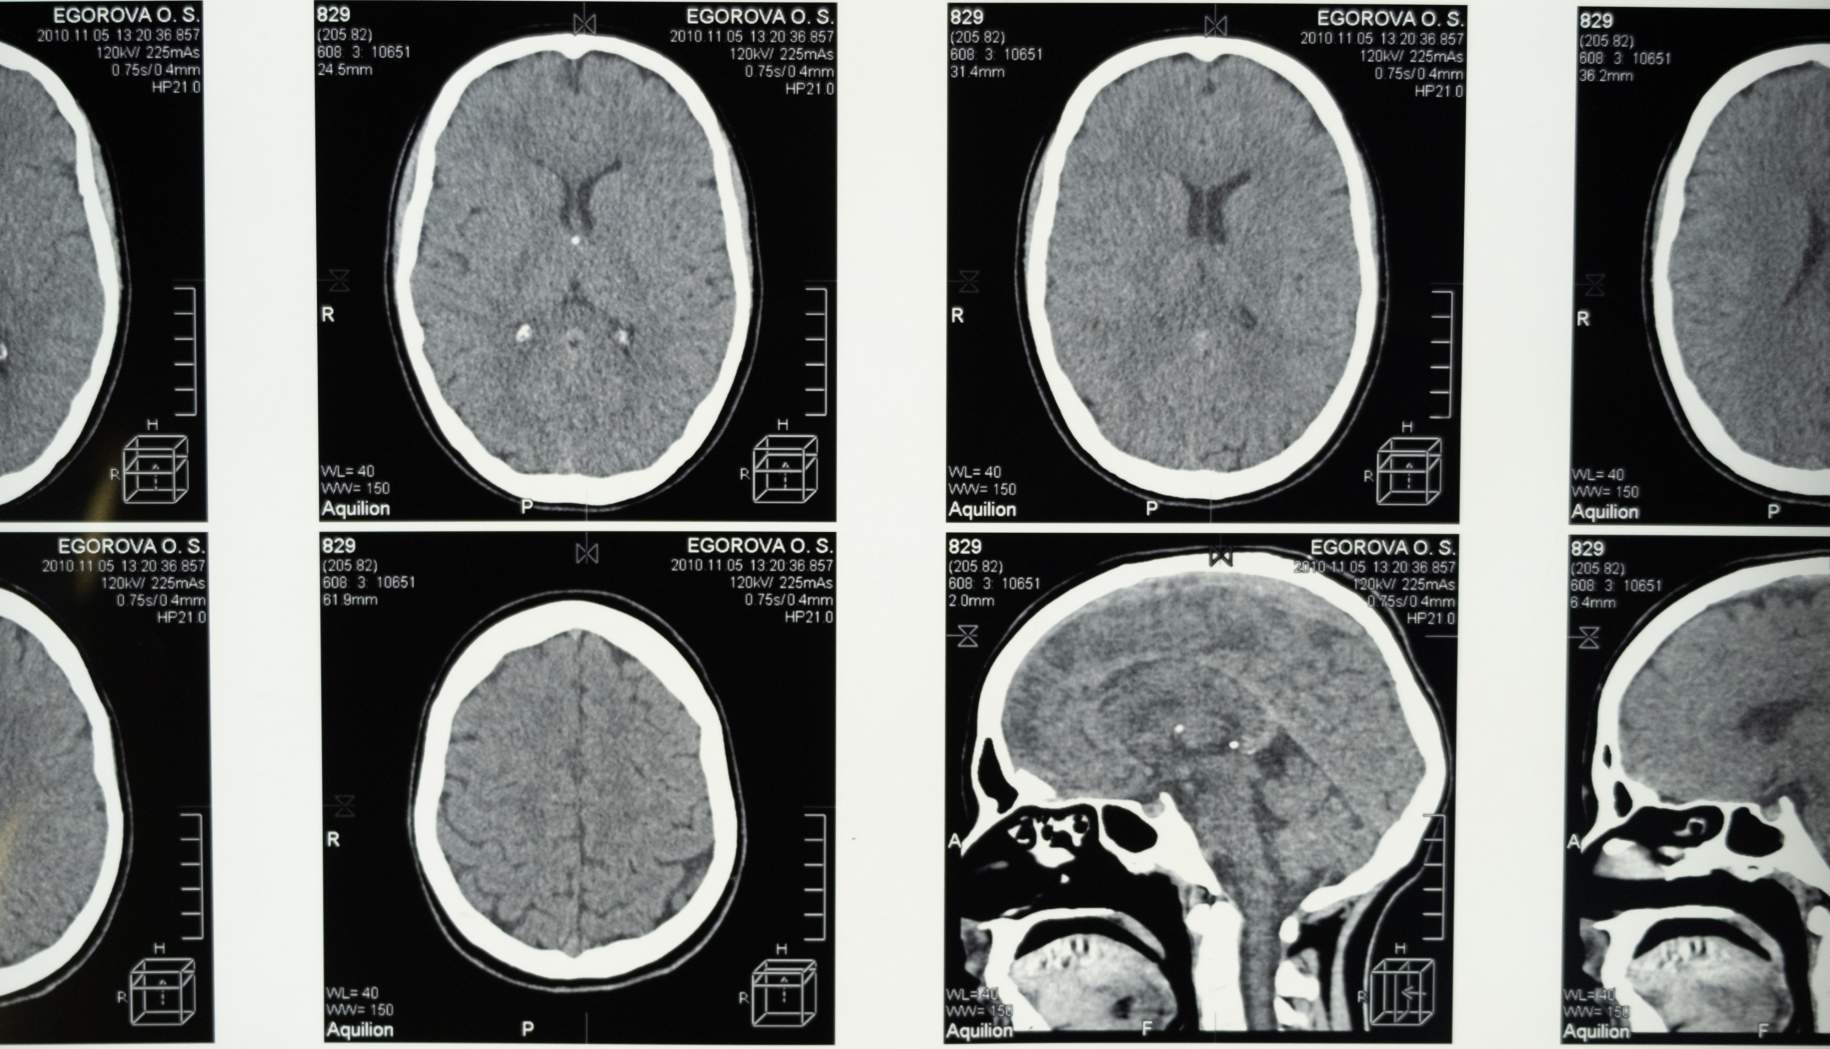

صورة 1. يوضح هذا الرسم وجود ورم سحائي يضغط على جذع الدماغ. إن محاولة الإزالة الجراحية الكاملة هي أفضل مسار للعلاج.